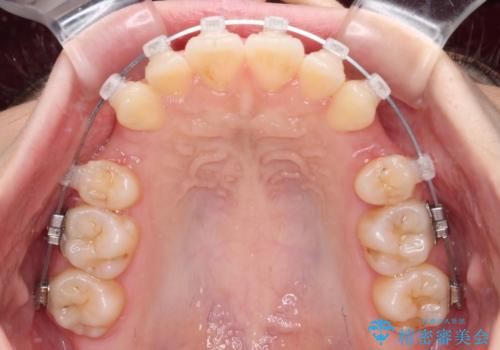

- 上下の前歯が突出しており、口が閉じにくいとのことで来院された患者様です。

上下前歯が著しく前突している状態であったので、上下左右の第1小臼歯4本を抜歯し、ワイヤー装置にて矯正治療を行うこととしました。

※写真にある上顎装置はメタルブラケットではありません。メーカー在庫都合などにより別の装置を使用しております。